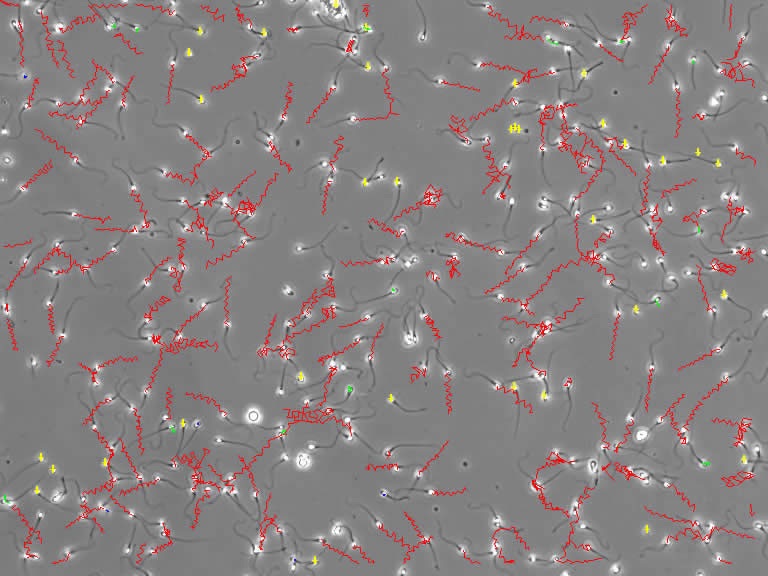

Computer programs have been developed to more accurately calculate sperm velocity. These devices, known by the acronym CASA (Computer Assisted Sperm Analyzer) are able to identify each sperm and track its movement. The path traveled is then represented on the screen by a line whose color depends on the speed.